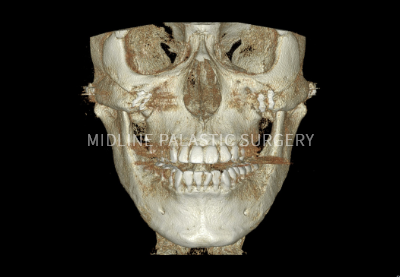

첫째, 3D-CT로 얼굴 뼈 촬영

둘째, CT, X-ray로 얼굴 뼈 전체 분석

셋째, 개개인에 맞는 섬세한 수술 계획

CT 촬영

3D-CT로 촬영한 데이터를 기반으로 얼굴뼈

전체를 정밀하게 분석하여 보다 안전하고

정확한 수술 계획이 가능합니다.